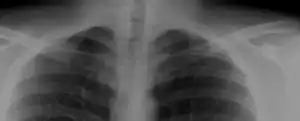

Bilateral, symmetric, full, ossified cervical ribs.

On imaging, cervical ribs can be distinguished because their transverse processes are directed inferolaterally, whereas those of the adjacent thoracic spine are directed anterolaterally.[10]